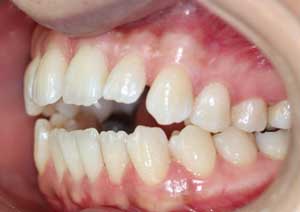

En orthodontie, une béance antérieure est une malocclusion caractérisée par l’absence de contact entre les incisives supérieures et inférieures lorsqu’on ferme les dents.

Traitement : Une ingression des molaires maxillaires avec une égression contrôlée du secteur antérieur a été réalisée à l’aide des arcs dits “Rocking Chair”, associés à des élastiques antérieurs portés de canine à canine, à droite et à gauche.

Cette mécanique permet de corriger la béance antérieure tout en conservant un contrôle précis de la position des dents antérieures et postérieures.

Après